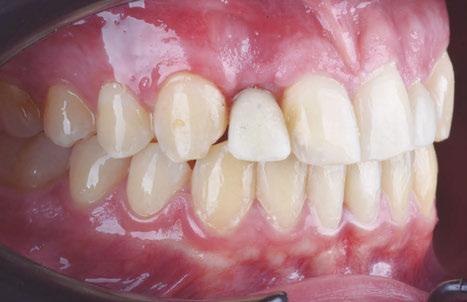

–Implante inmediato en incisivo lateral superior con técnica de «Socket Shield» y acceso vestibular para legrado de la lesión periapical, por el Dr. Ignacio Tormo Jiménez y cols. [106]